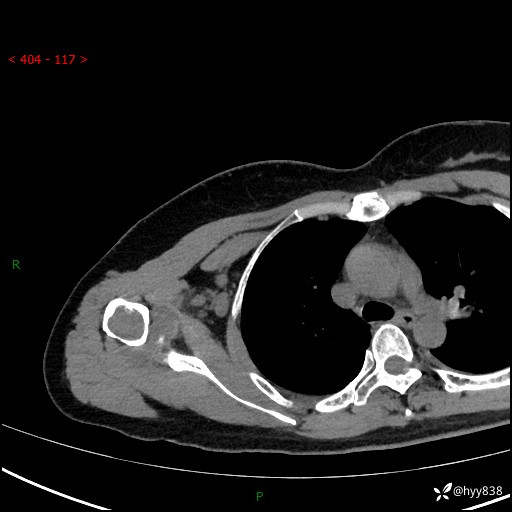

右肩关节平片

右肩关节CT平扫